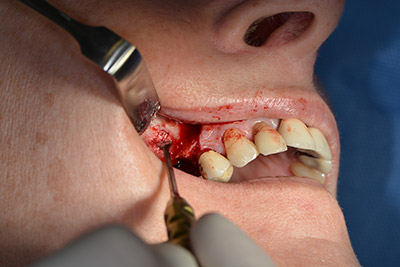

Surgical procedure for implantation

The classic incision (crestal, buccal relief) and the preparation of the mucoperiosteal flap enabled a good overview.

Sky implants (bredent) were used this case. The surgical protocol of these, specify pilot drilling at about 1200 rpm (Fig. 9).

The following holes were drilled at a reduced speed of 300 rpm. The Implantmed demonstrated its true capability at this stage. The surgical protocol can be preset – the various positions can be selected simply by pressing the “P” position of the foot control (Fig. 10 to 11).